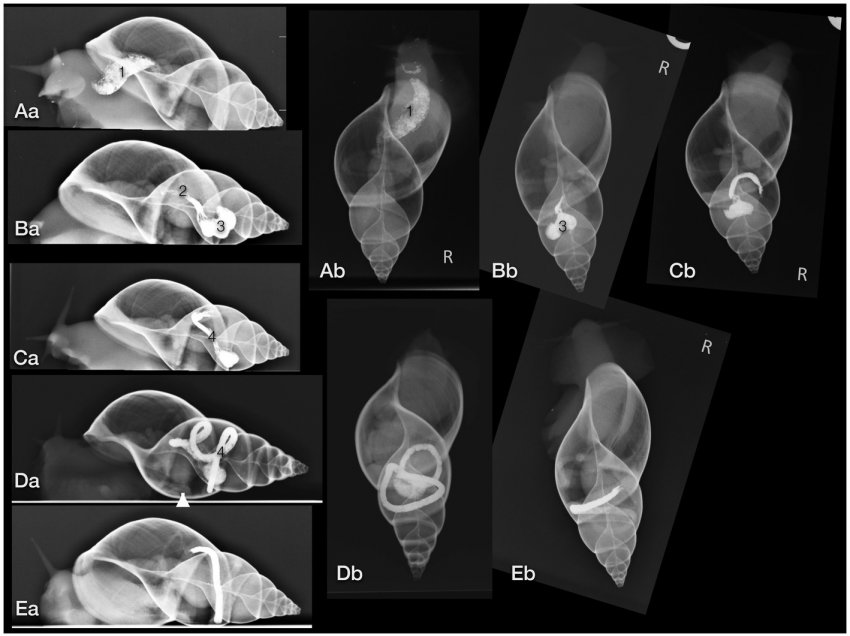

달팽이 CT찍을때 흔하게 일어나는일

환자가 영상촬영중 자기몸을 타고 올라감🤦♂️

가만히 있는동안에도 계속 주위를 두리번거림

아프리카거대달팽이(Achatinidae)의 비교 진단 영상학 Michaela Gumpenberger

#달팽이 #수의학 #カタツムリ #Snail_CT #獣医学